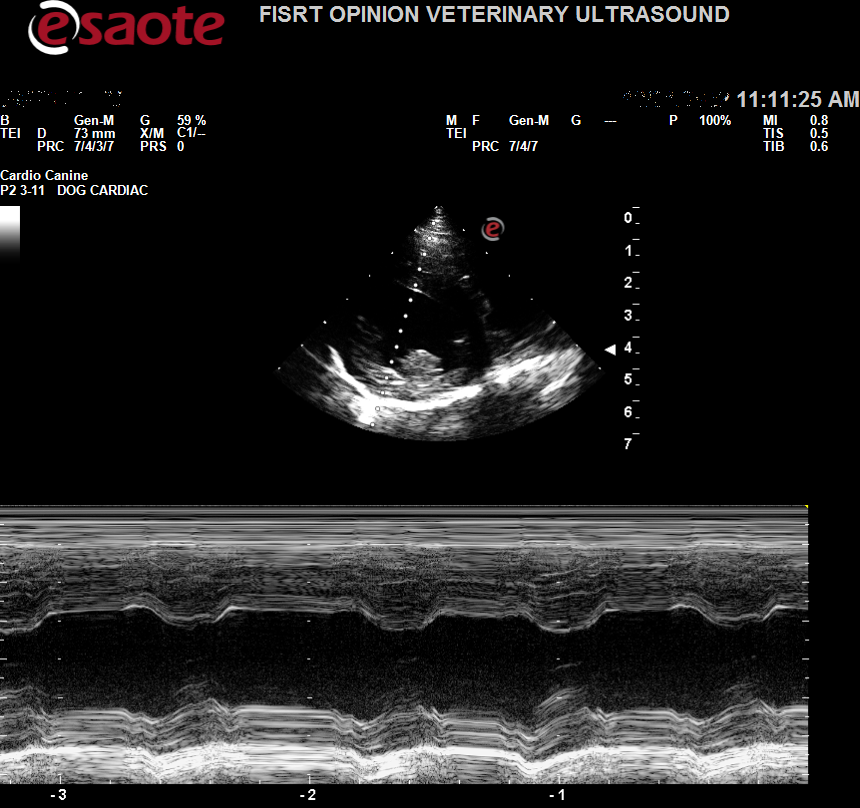

Images from the Sigma